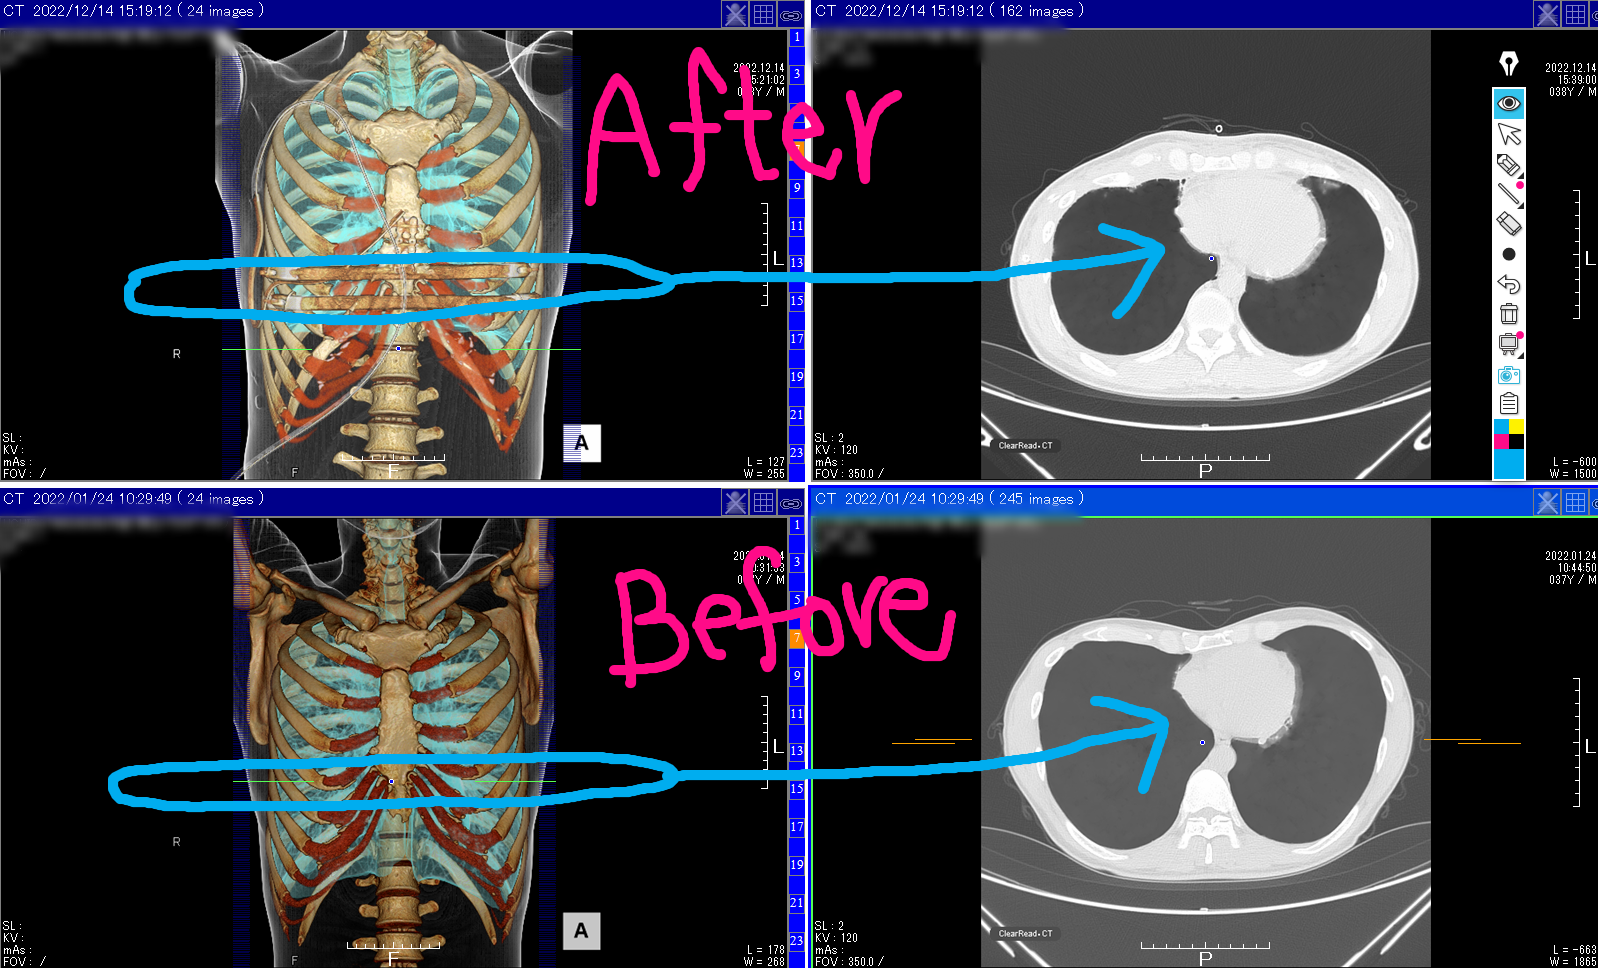

下の写真は手術前と手術後の写真ですが、今まで一番圧迫感を感じていた部分の比較写真になります。

CT画像を見ると心臓は大きくなっているように見えます。しかしもしかしたら、CT画像を撮る前に思い切り息を吸って止めた状態で写真を撮るのですが、術後は痛みで思い切り息を吸うのが少し甘かったのかもしれません。

少なくとも立ちくらみが無くなったのは、きっと心臓の体積が増加して血を送る量が増したからと推測してます。さらに言うと、これは関係ないかもしれませんが、ふだんの心拍数も下がった気がしています。血を送る量が増えたのだとすれば、心拍数も下がるの可能性はあるなと思っています。(気のせいかもですが)